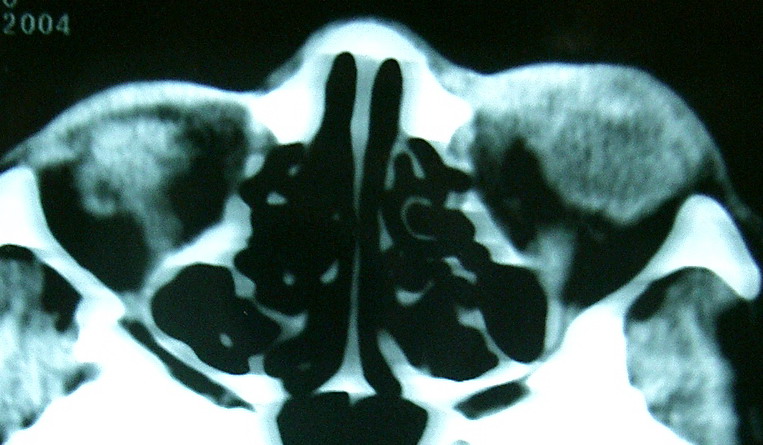

眼眶冠扫,平扫CT: 左眼球内上方可见不规则软组织块影,大小约2.5*1.0CM,与邻近组织分界不清,相邻之内直肌、上直肌增粗,眼环正常,眶壁骨质无破坏,左上颌窦底部可见粘膜增厚,其余副鼻窦未见异常。 IMP:1,左眼眶肿物;2,左上颌窦炎